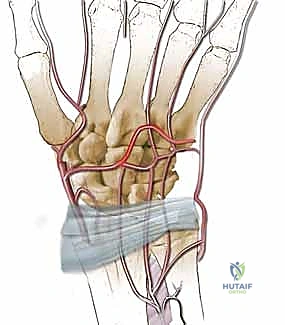

ثانياً: جراحة تقصير العظم الكبير (Capitate Shortening Osteotomy)

إعادة الدم وحده قد لا يكون كافياً إذا استمر الضغط الميكانيكي الهائل على العظم الهلالي الهش. يجب "تخفيف الحمل" (Offloading) عن العظم الهلالي لكي يشفى بسلام.

العظم الكبير (Capitate) هو أكبر عظام الرسغ ويقع مباشرة فوق العظم الهلالي. القوة المركزية لليد تنتقل من العظم الثالث في المشط، إلى العظم الكبير، ثم تصطدم مباشرة بالعظم الهلالي.

كيف تتم؟

1. يقوم الدكتور هطيف بإجراء قطع عظمي دقيق (Osteotomy) في العظم الكبير.

2. يتم إزالة شريحة صغيرة جداً من العظم (عادة بضعة مليمترات فقط).

3. يتم إعادة تثبيت العظم الكبير باستخدام مسامير دقيقة (Screws) أو دبابيس معدنية (K-wires).

4. النتيجة الميكانيكية: من خلال تقصير العظم الكبير، يتم نقل مسار توزيع القوة (Load Shift) بعيداً عن العظم الهلالي الضعيف، وتوجيهه نحو العظم الزورقي والعظام الأخرى. هذا الإجراء يمنح العظم الهلالي "مساحة للتنفس" والشفاء دون أن يتم سحقه تحت ضغط حركة اليد.

لماذا الدمج بين الإجراءين هو الحل الأمثل؟

الجمع بين تطويل (أو زراعة) العظم الوعائي وتقصير العظم الكبير يُعد ضربة مزدوجة لمرض كينبوك. الطعم الوعائي يعالج المشكلة البيولوجية (نقص الدم)، وتقصير العظم الكبير يعالج المشكلة الميكانيكية (الضغط المفرط). أثبتت الدراسات الطبية الحديثة أن هذا النهج المزدوج يوفر أعلى معدلات النجاح في الحفاظ على شكل العظم الهلالي، تخفيف الألم، ومنع تطور خشونة الرسغ.